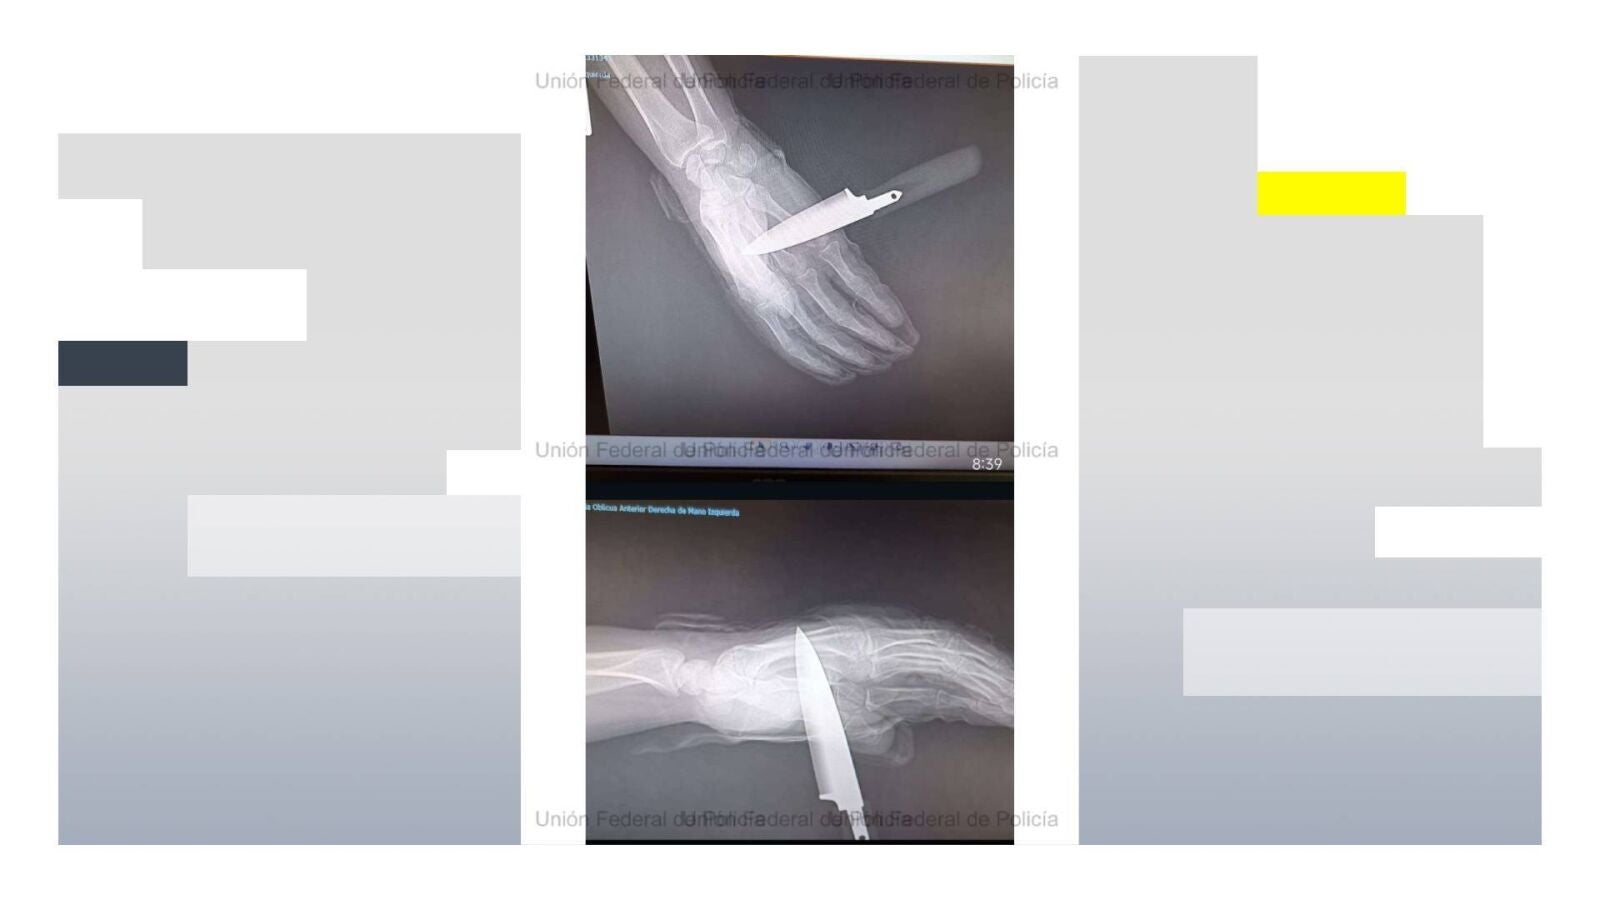

El agresor no se quedó atrás y, en lugar de frenar los ataques, trató de asestar una segunda puñalada. Aunque el agente logró repeler el golpe parcialmente, el arma blanca llegó a atravesarle la mano, provocándole una herida de consideración.

Por su parte, el agente herido tuvo que ser trasladado a un centro hospitalario con el cuchillo aún clavado en la mano.